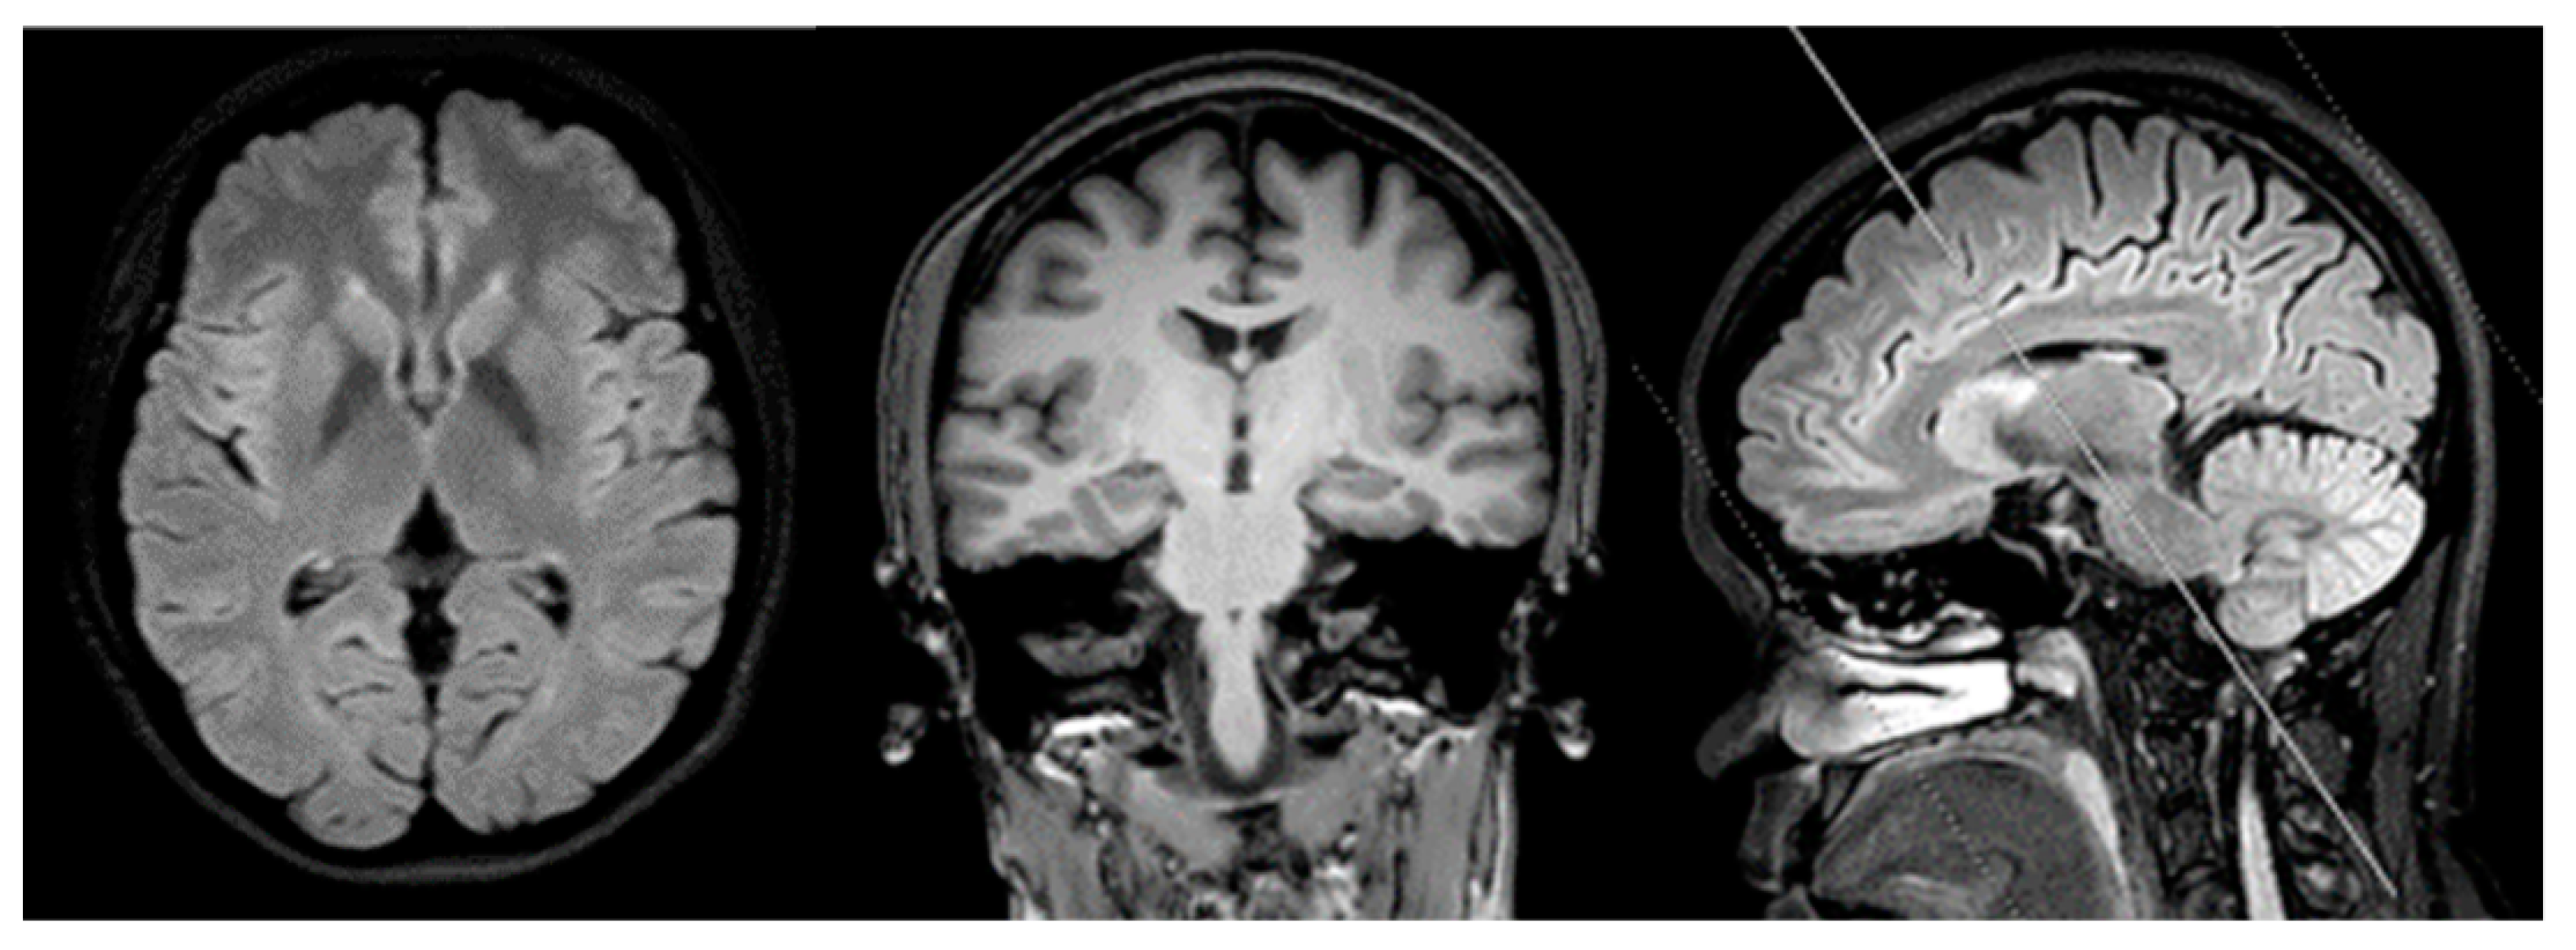

3. Clinical Symptoms of Patient